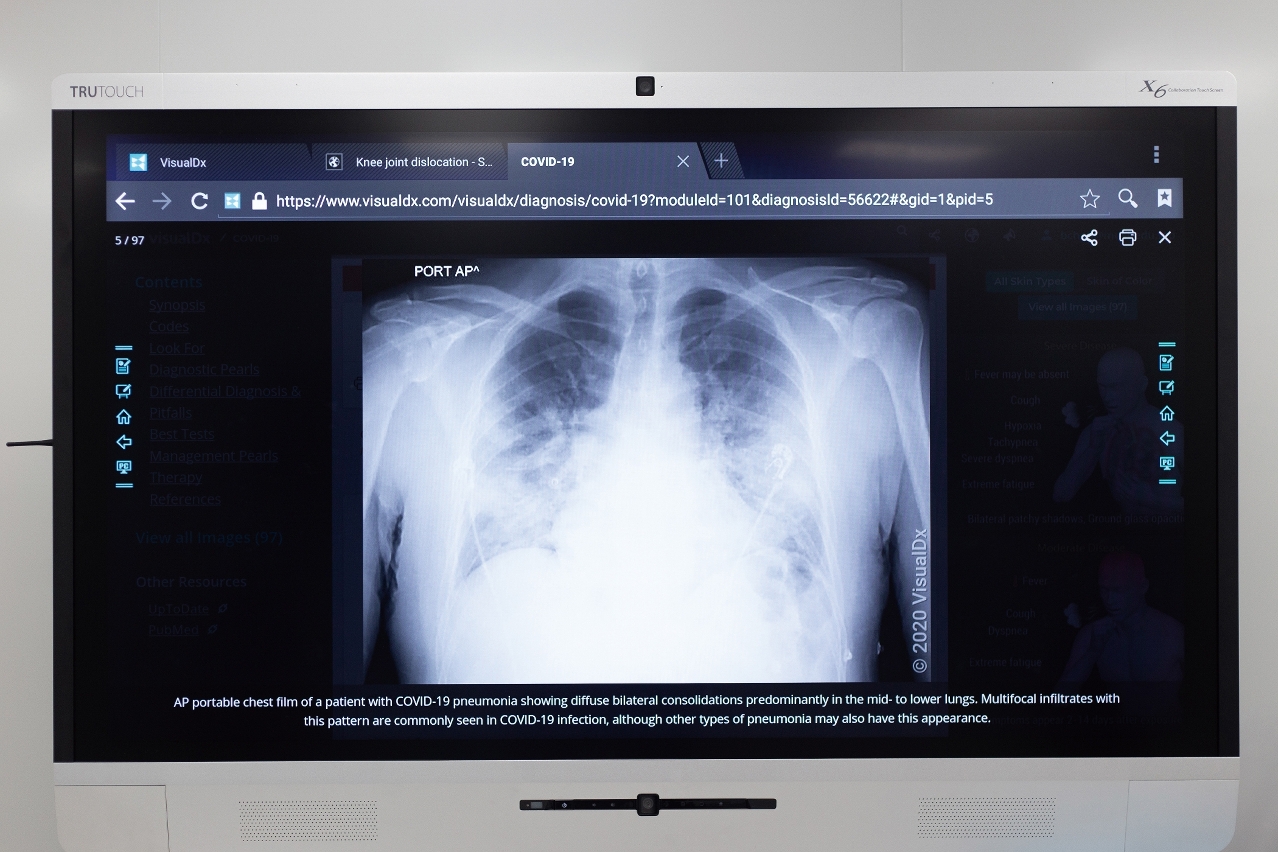

张康教授介绍,运用深度学习(Deep Learning)、迁移学习(Transfer Learning)、语义分割(Semantic Segmentation)等多种人工智能前沿技术,开发出基于胸部CT(Computed Tomography,电脑断层摄影)和X-ray(俗称「X光」)的新冠肺炎人工智能系统,可以对胸部医学影像进行快速辅助诊断。他说:「深度学习是近十年来,在人工智能领域发生的颠覆性技术,这技术以电脑作为媒介,模拟出人类大脑一样的记忆及思维。在此基础上,我们只要整合所有大数据及人工智能深度学习的演算法,通过训练就能够得到一个非常准确的新冠肺炎诊断工具。」

使用人工智能诊断技术,可以在病患的数百张胸部医学影像中快速准确地找出病灶。

AI诊断技术的出现,有效减轻医疗人力资源及物资的消耗,促进疫情诊断方向的全球化交流,对新冠肺炎的研究起到关键性作用。张康教授指出,每名病患都会拍摄数百张胸部医学影像,其中显示出病灶的便可能有数十张。「即使资历较深的医生,亦要约20分钟,才能通过胸部医学影像判断出患者是否感染了新冠病毒及肺部病灶所在,较为耗时。若使用AI诊断技术,则仅需20秒就可以完成辅助诊断。」AI诊断技术除有快速判断功能外,还可以对胸部医学影像的病灶进行自动识别、标注及定量分析,准确率达到90%以上,并可预测病灶的发展情况,有利医生及时诊治,亦有助医务人员进行药物效果评估,实现对新冠肺炎病患的全生命周期管理。